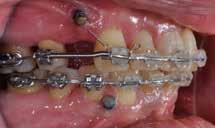

PATIENTTILFÆLDE 1

Patienttilfælde 1 (Fig. 1) er en 37-årig kvinde, henvist efter succesfuld behandling af stadie 3-parodontitis. Der er nu sundt

Før behandling

parodontium, ingen pocher over 4 mm, og både blødnings- og plakindeks er under 10 %. Patienten er motiveret for ortodontisk behandling, da hendes tænder er vandret over tid, delvist som følge af reduceret parodontium.

Der ses anterior trangstilling i begge kæber og overerupterede 1+1 og 2,1-1,2, hvilket resulterer i dybt bid med 2- tæt på ganepåbidning. Der er normale sidetandsrelationer, men der ses 5 mm horisontalt overbid (HOB) og 7 mm vertikalt

overbid (VOB). Papillen mellem 1+1 er betydeligt reduceret pga. fæstetab, og de mesialt kippede 1+1 har resulteret i en ”dark triangle”. Den facioorale funktion er for nuværende i.a. Panoramarøntgen (Fig. 1, I) viser marginalt knogletab i begge kæber og fravær af 8,7+7,8 og 8,7-8.

Objektivt anbefales behandling af det dybe bid, som ubehandlet forventes at forværres yderligere over tid. Patienten har ønske om behandling med æstetisk ortodontisk apparatur, alignere, og det vurderes muligt at behandle malokklusionen med alignere. Dog anbefales det generelt, at alignere undgås eller benyttes med væsentlige modifikationer af alignerens retention ved tandmobilitet, da dette ellers kan medføre jiggling, når aligneren tages af og på mange gange dagligt. På den anden side er der nogen evidens for, at alignerbehandling er associeret med bedre renhold og parodontal sundhed sammenlignet med fast apparatur (16).

Der planlægges alignerbehandling af begge kæber med intrusion af 1+1 og 2,1-1,2, nivellering af trangstilling UK med interproksimal reduktion (IPR) (Fig. 2 A, B) og senere IPR OK for reduktion af dark triangles mellem incisiverne efter nivellering. Patienten instrueres i at benytte alignere 20-22 timer/ dag med alignerskift hver 7. dag, og patienten ses hver 3.-8. uge under forløbet. Den første alignerserie består af 16 alignere for nivellering OK/UK og IPR i UK (Fig. 2). Efter denne serie planlægges IPR mellem incisiverne i OK for reduktion af dark triangles (Fig. 3) samt yderligere intrusion af OK og UK-fronten i 12 refinement-alignere. Patienten udviser god kooperation og er meget tilfreds med alignerapparaturet, som er mindre synligt end det faste apparatur (Fig. 4).